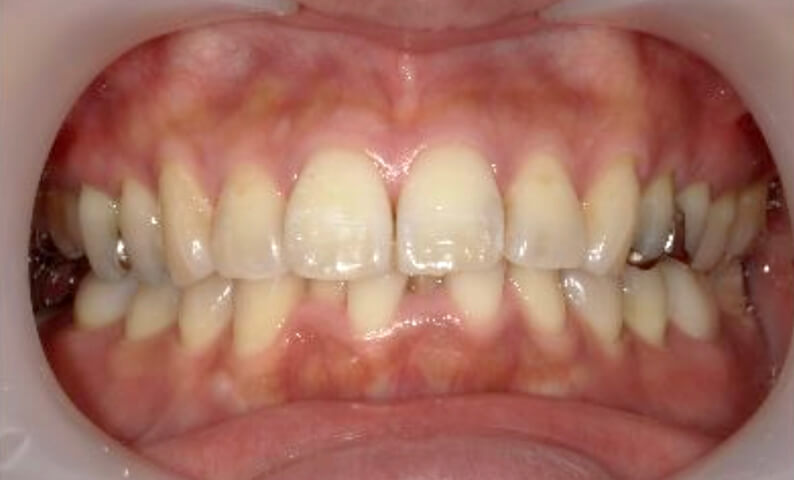

症例_003 下顎だけの部分矯正

治療期間:10ヶ月金額:24万円+税女性前歯のガタガタ下の前歯だけ上顎は補綴治療中

| Before | After |